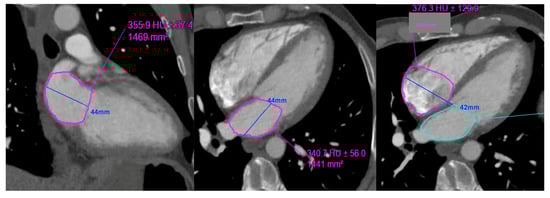

Figure 4.

Example of left and right atrial planimetry in a 50-year-old male with body surface area of 1.9 (height 173 cm, weight 76 kg).

Left atrial volume: (0.85 × area 1 (2 chamber) × area 2 (4 chamber)) ÷ shortest LA long axis length: |

0.85 × 14.7 × 14.4 ÷ 4.4 = 40.8 mL. LAVi = 21.4 mL/m2 |

Right atrial volume: (0.85 × (RA 4 chamber area)2) ÷ RA long axis length: |

0.85 × (16.1) 2) ÷ 4.2 = 52.45 mL. RAVi: 27.6 mL/m2 |

LAVi: Left atrial volume indexed; RAVi: Right atrial volume indexed.